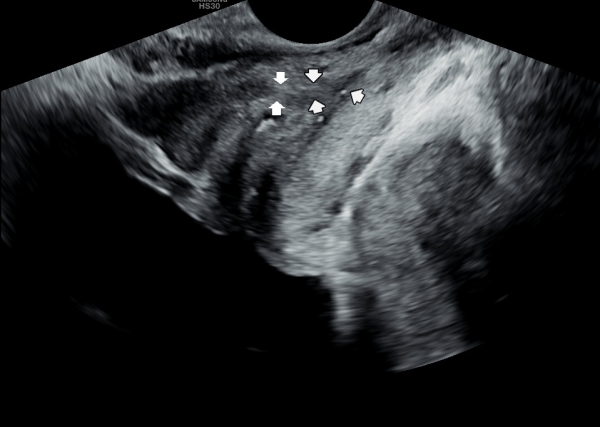

주 2~3회 전립선의 표적 치료 약 5개월후 추적 경직장 전립선의 초음파 사진상 사정관 입구에 있던 결석이 감소 되고 사정관내 탈락된 상피 세포가 치료된 사진입니다.

Follow-up transrectal ultrasound image of the prostate after approximately 5 months of targeted prostatic treatment (2–3 times per week), showing a reduction in the calculi at the ejaculatory duct opening and improvement in the exfoliated epithelial cells within the ejaculatory duct.

그러나 바쁜 일상 생활과 빈뇨와 배뇨장애 그리고 야간 빈뇨 등의 증상이 좋아 지고 나서 전립선의 관리를 하지 못할 경우 탈락된 상피세포가

사정관의 입구와 사정관 주위에 다시 침착하고 점점 만성 골반통 증후군과 만성 전립선염과 전립선 비대증 그리고 전립선의 악성 종양이 생길수

있는 추적 경직장 전립선의 초음파 사진입니다.